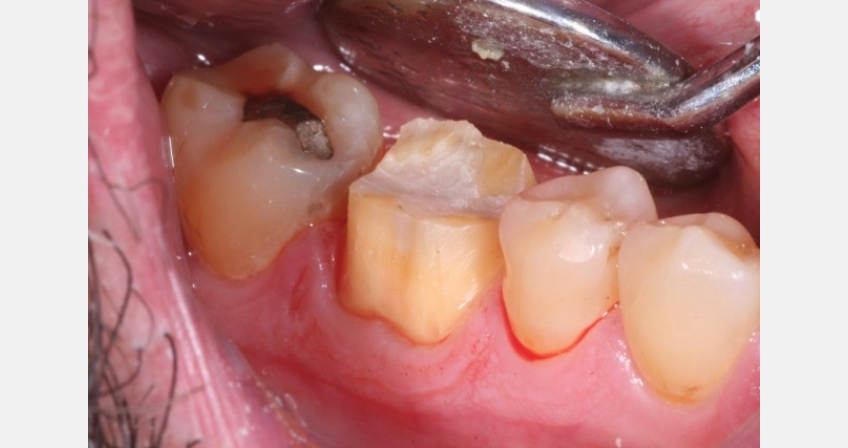

- Rough finish the margins with this bur and round off any immediate edges or ledges.

- Switch to a larger, finer diamond bur to refine and smooth margins and preparation overall.

- Done!